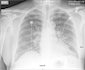

View Case #24001

A man in his 60s presents with progressive shortness of breath.